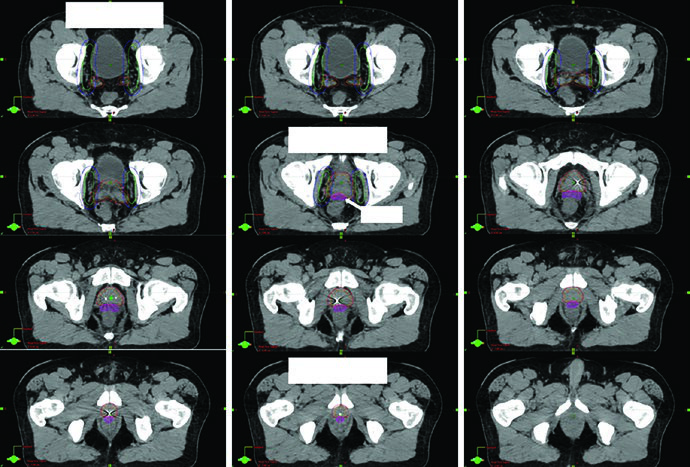

A Fig. 25.3 mostra esse raciocínio com clareza. As imagens seguem da porção caudal para a cranial em uma TC de 2 mm com protocolo de bexiga cheia. A legenda exibe o CTV inicial em azul e a modificação manual do PTV em vermelho, exatamente para evitar excesso de dose no reto quando a expansão gera cranialmente aquela configuração em halter na região anterolateral retal. Não é só uma figura bonita. É um exemplo de como a expansão automática precisa ser revisada quando a anatomia operada cria espaços novos e contornos contraintuitivos.

A Fig. 25.4 aprofunda esse ponto ao projetar o PTV em vistas ortogonais. Diferentemente do plano para próstata intacta, o pós-operatório inevitavelmente aproxima o volume da bexiga e do reto para cobrir possíveis focos microscópicos, incluindo o espaço perirretal anterior, a anastomose vesicouretral e os novos planos criados entre bexiga posterior, assoalho pélvico e VUA. A legenda destaca a sobreposição do PTV com reto em verde e bexiga em amarelo. A inspeção 3D garante que o limite anterior do PTV afile de forma progressiva acima da sínfise púbica. Quando essa transição fica abrupta, as mudanças diárias de enchimento vesical tornam o targeting mais suscetível a erro.